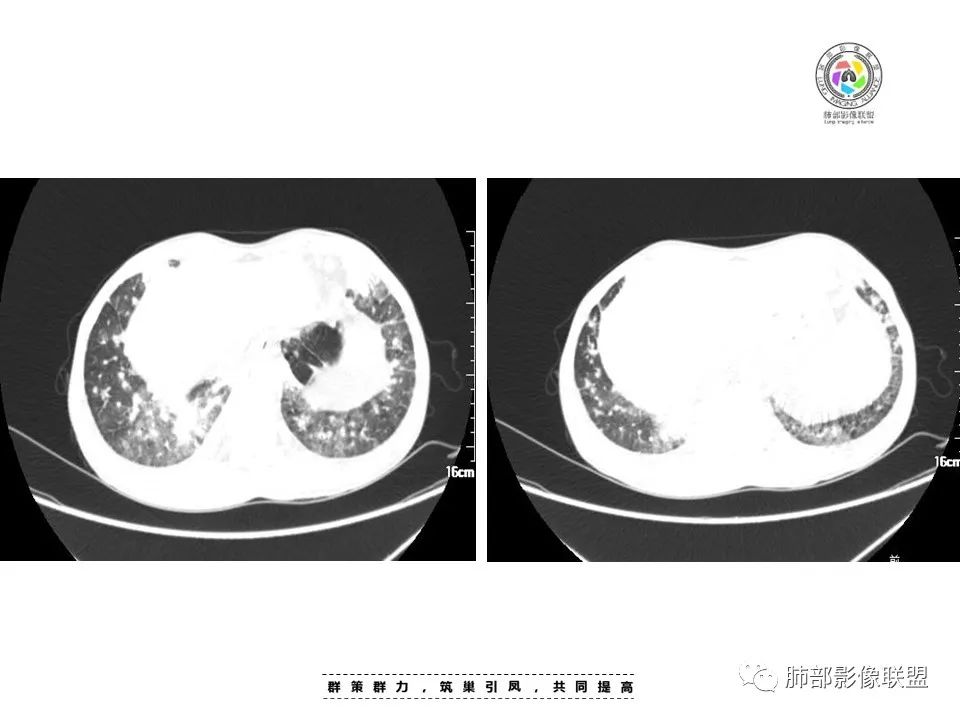

两肺弥漫性性结节状、小片状及片状带晕的病灶,煎蛋征、点晕征,主要分布两肺中下叶,病灶周围小叶间隔增厚呈网格状影,部分病灶累及胸膜,伴两侧胸膜增厚。

2.本例双肺小叶间隔增厚明显,多发结节影及片状实性密度影,沿血管支气管束分布为主,两侧较为对称,病灶多环以磨玻璃晕,边界不清。

双侧胸腔少量积液。双肺门及纵隔未见明确肿大淋巴结,纵隔结构间隙模糊。

3.有学者将这种具有沿双肺支气管束分布的实性密度片影描述为“火焰征”,认为具有一定特征性,单就影像表现而言,这种影像表现也可以见于其他病损或多种病理改变的叠加。

1.结节型:两肺沿支气管血管束分布的结节影,呈火焰状或星芒状、挂果征,局部周围出血磨玻璃影(肺泡出血或水肿)。

斑片渗出影,部分融合呈“火焰样”,同时有火焰样结节,小叶间隔增厚等表现。

还可以有纵隔及腋下淋巴结增大,胸腔积液等表现。